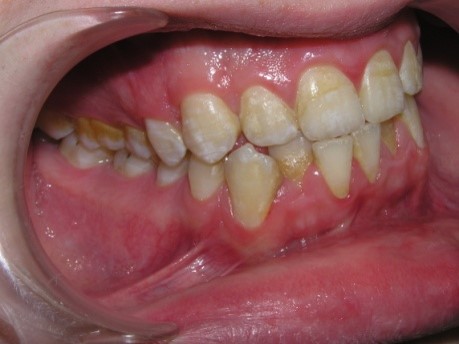

Pic.10. Lingual position of teeth 32 and 42.

The crowding of the lower frontal

teeth reduces the resistance of the teeth to the carious process, creates

conditions for the development of periodontal diseases, and the formation of

periodontal pockets.